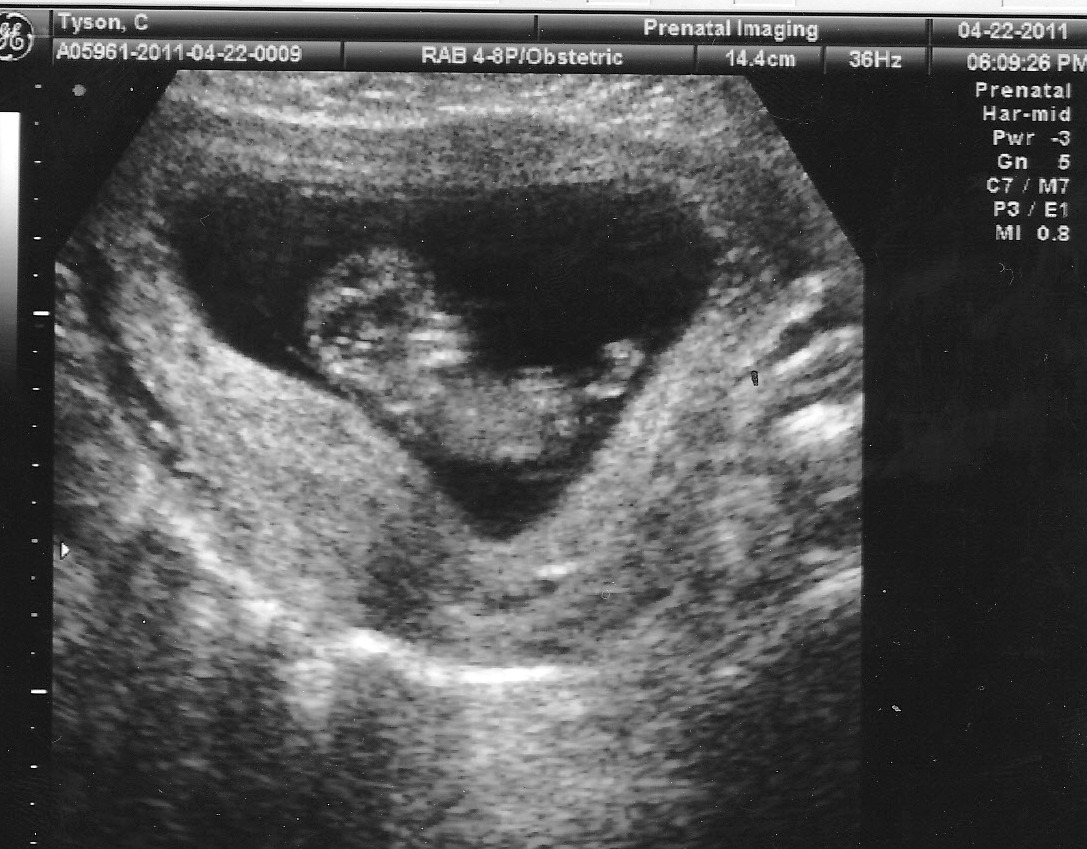

Tuesday was my last doctor's appointment before I move to Mississippi (which occurs in T-minus 7 days)! Somehow, with maybe a little begging and an "I want to make sure everything looks normal before I have to find a new OB" line, I managed to weasel myself into getting another ultrasound!

Justin and I were hoping to find out Little's gender at this appointment, but have the nurse put it in an envelope for us to open this weekend together. Unfortunately, Little was not being very cooperative. At first glance the cord was between the legs, then a hand, and finally ended up cross-legged face down, butt sticking straight up. The nurse tried, and tried, and even had me stand up and wiggle, but nothing motivated this kid to reveal secrets.

Some say, due to Little's modesty, they think it is a girl. We shall see. We've come to the conclusion, if this uncooperative streak keeps up and we are unable to find out the gender at the next ultrasound, we're just going to wait until Little's in our arms to know.

The ultrasound showed baby was developmentally a week behind my estimated due date, which matched up perfectly with the first ultrasound. When I went in for my first appointment, the gestational age of Little was 7 weeks 1 day, but according to my estimated due date I was supposed to be 8 weeks 1 day along. The nurse said the growth between the ultrasounds was right on target and everything looked as normal as she could tell for a baby of 15 weeks. With all said and done, my estimated due date is now inching closer to Thanksgiving and is now coming in at November 15th.

According to my new due date, I'll be 19 weeks at my next appointment in McComb, MS. Maybe since Justin will be with me Little will cooperate and clue us in on what accent color should be chosen for the nursery. :)